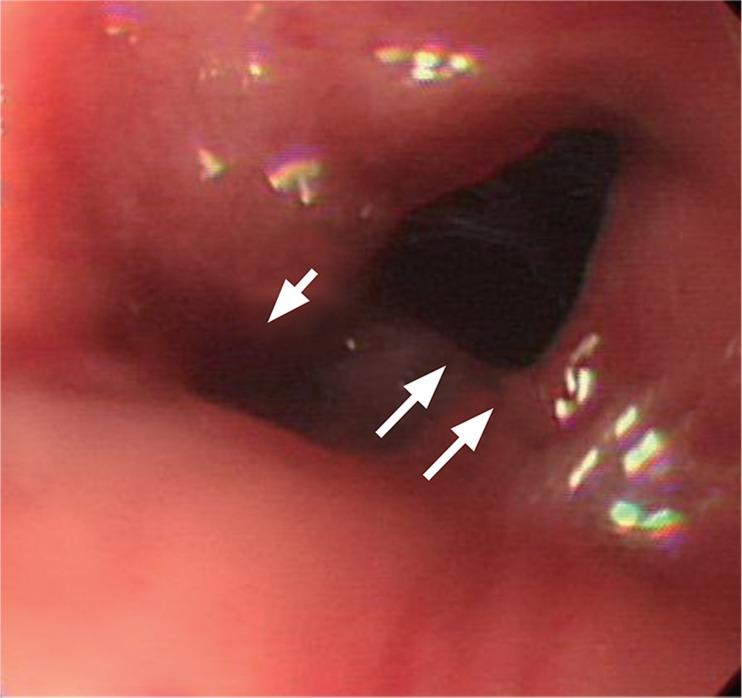

Successful management of colonic perforation with a covered metal stent.

Self-expandable stents are widely available for the treatment of perforation of the gastrointestinal tract. Because of the risk of migration, there has been no report of the use of self-expandable stents for the treatment of perforation of the colon or rectum. This is a report of successful treatment of iatrogenic colonic perforation during balloon dilatation of anastomotic stricture with a fully covered stent. Fully covered, self-expandable metallic stents can be considered useful tools for management of this condition.